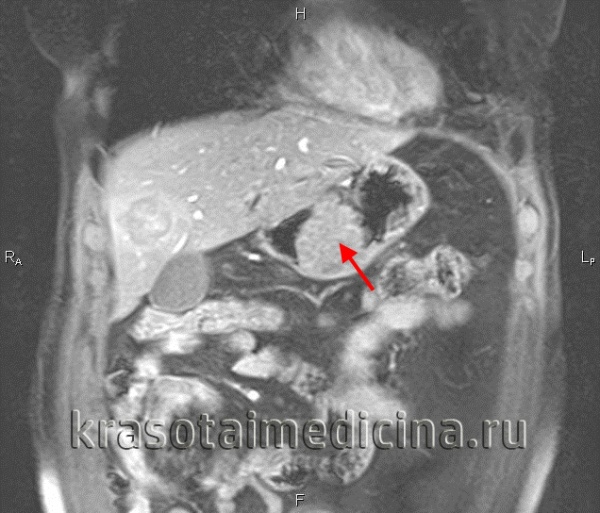

Далее распространение продолжается в узлы чревного ствола, в селезеночную цепь и печеночную цепь вокруг ворот печени. Иногда отмечается увеличение узлов в левой надключичной области глубоко к грудинному месту прикрепления (узел Вирхова). Рак желудка также локально распространяется сквозь стенку желудка в сальник, печень и поджелудочную железу. Фрагменты опухоли могут обрываться и рассеиваться широко по перитонеальному пространству, вызывая злокачественные асциты и опухоли Крукенберга на поверхности яичников. Метастазы, переносимые с кровью, особенно часты в печени, но также встречаются метастазы в легких. Нечасто происходят метастазы в кости, метастазы в центральную нервную систему являются редкими.

При своем росте опухоль может прорастать не только все слои стенки желудка, но и соседние органы (печень, поджелудочная железа, селезенка, поперечная ободочная кишка, диафрагма). Опухоль может давать метастазы. Различают три пути метастазирования: по лимфатическим, кровеносным путям и имплантационное мстастазирование по брюшине (опухоль прорастает серозную оболочку).

Метастазы во внутренние органы (печень, поджелудочная железа, почки, надпочечники и др.) имеют значение в том смысле, что. как правило, такие больные бывают неоперабельными. Для дооперационной диагностики IV стадии рака нужно знать некоторые типичные метастазы: Вирхова — в область левого надключичного пространства, Крукенберга — в яичники, Шницлера — в дугласово пространство В некоторых случаях при наличии солитарного метастаза в печень или поджелудочную железу выполняют комбинированную условно-радикальную операцию — резекцию желудка и печени или резекцию желудка и поджелудочной железы.